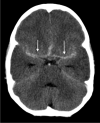

Tuberculosis (TB) remains one of the major public health threats worldwide, despite improved diagnostic and therapeutic methods. Tuberculosis is one of the main causes of infectious disease in the chest and is associated with substantial morbidity and mortality in paediatric populations, particularly in low- and middle-income countries. Due to the difficulty in obtaining microbiological confirmation of pulmonary TB in children, diagnosis often relies on a combination of clinical and radiological findings. The early diagnosis of central nervous system TB is challenging with presumptive diagnosis heavily reliant on imaging. Brain infection can present as a diffuse exudative basal leptomeningitis or as localised disease (tuberculoma, abscess, cerebritis). Spinal TB may present as radiculomyelitis, spinal tuberculoma or abscess or epidural phlegmon. Musculoskeletal manifestation accounts for 10% of extrapulmonary presentations but is easily overlooked with its insidious clinical course and non-specific imaging findings. Common musculoskeletal manifestations of TB include spondylitis, arthritis and osteomyelitis, while tenosynovitis and bursitis are less common. Abdominal TB presents with a triad of pain, fever and weight loss. Abdominal TB may occur in various forms, as tuberculous lymphadenopathy or peritoneal, gastrointestinal or visceral TB. Chest radiographs should be performed, as approximately 15% to 25% of children with abdominal TB have concomitant pulmonary infection. Urogenital TB is rare in children. This article will review the classic radiological findings in childhood TB in each of the major systems in order of clinical prevalence, namely chest, central nervous system, spine, musculoskeletal, abdomen and genitourinary system.